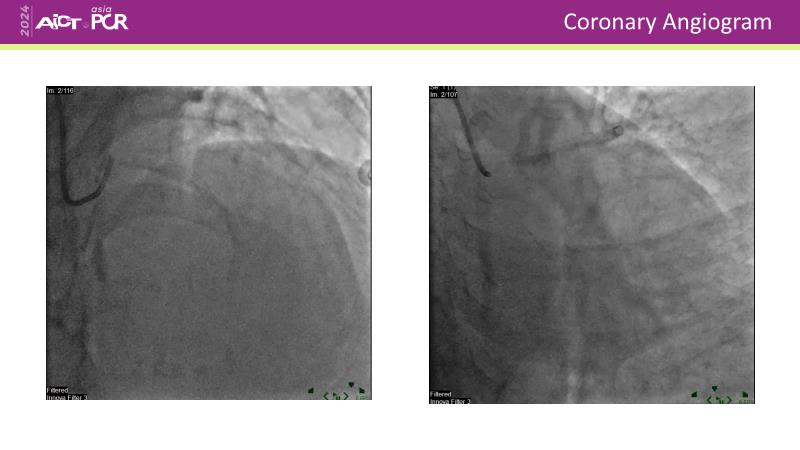

Discover the power of drug-coated balloon (DCB) technology in modern PCI. Understand the mechanism of action, including antiproliferative agents, drug transfer to the vessel wall, and effective inhibitory level and duration of vessel wall retention. Learn how IVUS can guide optimal lesion preparation, and explore the criteria for delivering effective DCB treatment.

- To learn how IVUS can guide optimal lesion preparation

- To learn the criteria for optimal lesion preparation prior to DCB application